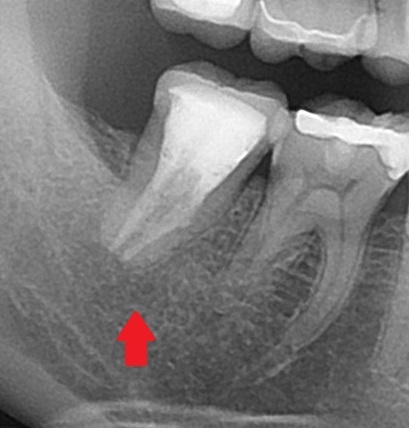

「歯を抜かないといけない」と言われたが、当院で抜かずに終えました。